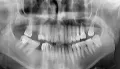

У меня на нижней челюсти 44 зуб (первый коренной зуб, сразу же после клыка). 8 лет назад он у меня сломался, потом лечила его у трех специалистов, зуб мертвый. Три дня болело у корня зуба, пошла к дежурному врачу, настояла на рентгене. На снимке было видно темное пятно у корня зуба. Врач сказала, гранулема, и нужно удалять зуб. Так как хотела избавиться от боли, послушала врача, зуб удалили. Теперь жалею, что на видном месте пустота (нельзя теперь широко улыбаться).

Конечно, необходимо было услышать несколько мнений. Сейчас уже поздно об этом говорить, но в 90% случаях зубы удаляются при обширном гранулирующем процессе. Причина данного воспаления некачественное лечение каналов. Задумайтесь об этом и обращайтесь на лечение впредь только к квалифицированным специалистам. Через три месяца на место удаленного зуба необходимо установить имплантат.